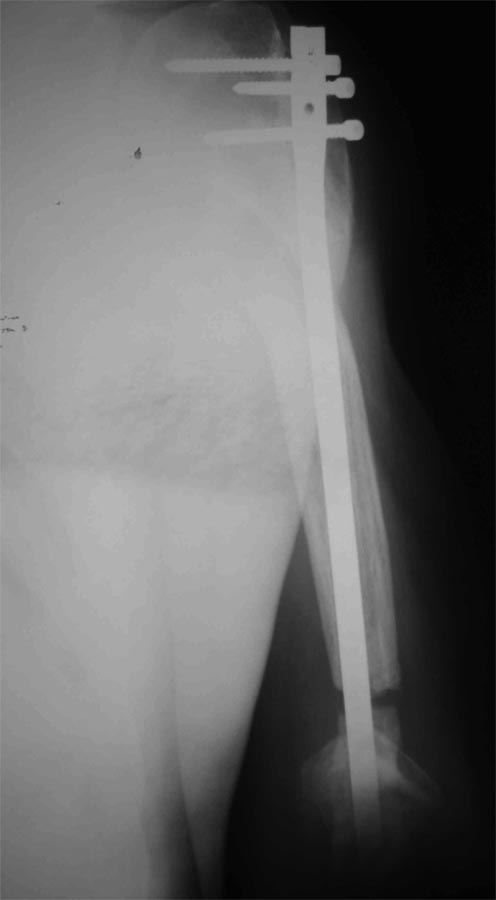

Уважаемые коллеги! Пациент получил травму около 1 года назад, выполнялся остеосинтез по поводу переломов лучевой, бедренной, плечевой костей.

Обратился в связи с выраженной контрактурой в коленном суставе (сгибание 10-15 град)и практически отсуствием самостоятельного отведения плеча. Снимки представлены. Планируем выполнить реостеосинтез плеча (скорее всего этим же стержнем, так как другого нет) с коррекцией положения отломков в проксимальном отделе и сближением отломков в области диафиза.

- необходима ли будет костная пластика в области диафиза плеча?

- адекватен ли по Вашему мнению реостеосинтез стержнем?